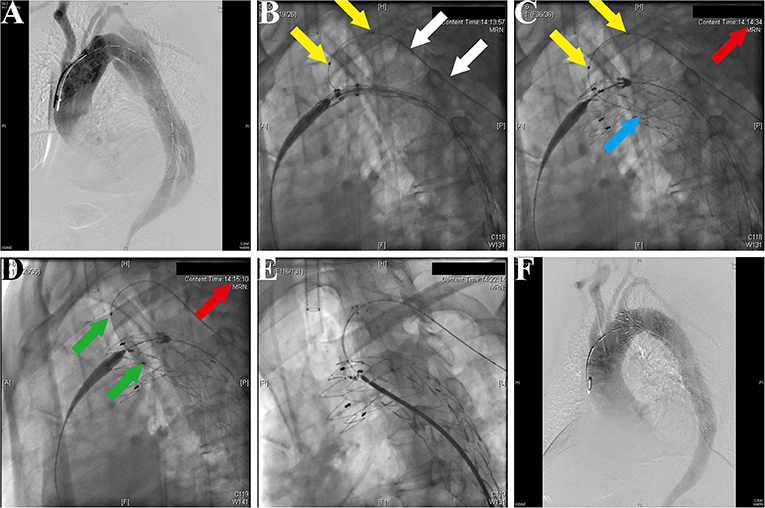

After general anesthesia, the left femoral artery and left brachial artery were exposed, cannulated with a 24-Fr sheath and an 8-Fr sheath separately. Through the access of the femoral artery, the digital subtraction angiography (DSA) was made by a pigtail catheter (Figure 3A). The location of prefenestration was determined by preoperative CT angiography (CTA) and intraoperative aortography. The prefenestrations were made on Valiant Captivia Stent Grafts with a 5 × 5 mm cross (Supplementary Movie 1). The range of oversizing rate was 5 to 20% according to the experience of operators. Before the stent graft was reloaded into a delivery system, the tip of a guidewire (RF*GA35153M, Terumo, Japan) was induced through the fenestration for the purpose of traction from the aorta to the LSCA (Supplementary Movie 2). After preparation, the traction guidewire was induced from femoral access and caught from the brachial access (Figure 3B, white arrows). Then, a peripheral angioplasty balloon catheter (Mustang, Boston Scientific, Natick, Massachusetts, USA) was induced through the guidewire in order to (1) prevent the cutting effect on the LSCA and (2) prepare for revascularization of the LSCA (Figures 3B,C, yellow arrows). When the stent graft was induced beneath the LSCA, multiple observation perspectives from DSA were adjusted to prove the traction guidewire was not twisted. The key step then was performed by one operator and two helpers. The operator controlled the delivery system and released the main stent graft; helper no.1 controlled the super stiff guidewire and helper no. 2 controlled the traction guidewire to make sure that they were in place (Figure 3C). After the release of the main stent graft, the fenestration was softly enlarged by the balloon at 6–8 atmospheres (Figure 3D) and the Fluency Plus Stent Graft was directly induced through brachial access and again flared by a peripheral angioplasty balloon at 8–10 atmospheres (Figure 3E). The branch stents were 10–20% oversized to the LSCA. When there was a need to cover LCCA for a sufficient landing zone, additional LCCA access was exposed for a traction guidewire. The choice of LCCA branch stents was according to the preference of operators, in which there were Viabahn (Gore, Flagstaff, Arizona, USA) and LifeStent (Bard Peripheral Vascular, Germany, UK) devices. The definition of technical success was the successful implantation of main and branch stents without any type I/III endoleak, migration (Figure 3F), or any other immediate major adverse cardiac and cerebrovascular events (MACCE).

Figure 3. Fluoroscopic demonstration of the fenestrated stent graft delivery and engagement. (A) Morphological feature of aortic dissection through the digital subtraction angiography. (B) Delivery and advancing of the main stent graft into the proper landing zone. A traction guidewire was established through the left subclavian artery (LSCA) (white arrows). An angioplasty balloon catheter was prepared for the expansion of the fenestration (yellow arrows). (C) The main stent graft was released and the LSCA was temporarily covered. The traction guidewire was still in the stent graft (blue arrow). (D) Angioplasty of the LSCA through the guidewire from left brachial access (green arrows). The duration from coverage of the LSCA and revascularization was 36 s (red arrows, 14:14:34–14:15:10). (E) Deployment and engagement of the LSCA branch stent graft. (F) Final aortogram demonstrating patent arch branches and exclusion of the false lumen.

First, the location of the fenestration was confirmed by the traction guidewire (Figure 3B), which simultaneously reduced the endovascular procedure time and risk of dislocation between the branch artery and fenestration. This design was inspired from the construction of single-branched Castor stent graft, which is confirmed to be effective and safe for aortic arch pathologies (20). The guidewire preloaded in the main stent graft could help the operator to easily place the stent graft in the designed location (Figure 3B, white arrows). In the previous study, a radiopaque marker was always needed for the right implantation of stent grafts (21). However, plenty of time used for markers increased the burden of patients. According to the previous studies about handmade fenestration for the LSCA, the mean operation time was 171–176 min, which was significantly longer than our data (mean operation time, 125 min) (22, 23).

Second, the revascularization of the LSCA/LCCA was literally rapid around 60 s in this study (Figure 3D; Table 2). Given the importance of supra-arch vessels, the rapid LSCA/LCCA revascularization is demanding study (24). In this study, the prefenestration had a 5 × 5 mm hole, which allowed the blood flow to come through. More importantly, when a main stent graft was implanted, the balloon was already prepared for rapid revascularization (Figure 3C). Although the traditional fenestration technique does not need to consider the time of revascularization, unsuitable fenestration may cause unexpected coverage or endoleak (25). In terms of the in-situ fenestration technique, it takes time to penetrate the main stent grafts, which may increase the risk of cerebral infarction (24, 26).